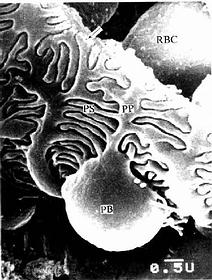

图15-7 兔肾小体扫描电镜像示足细胞

PB足细胞体,PP初级突起,PS次级突起,RBC红细胞,

↑基膜(河北医学院电镜供图)

(2)肾小囊(renal capsule)又称Bowman囊,是肾小管起始部膨大凹陷而成的双层囊,似杯状,囊内有血管球(图15-3,15-4)。肾小囊外层(或称肾小囊壁层)为单层扁平上皮,在肾小体的尿极处与近端小管上皮相连续,在血管极处反折为肾小囊内层(或称肾小囊脏层),两层上皮之间的狭窄腔隙称肾小囊腔,与近曲小管腔相通。内层细有胞形态特殊,有许多大小不等的突起,称为足细胞(podocyte)(图15-5,15-6)。足细胞体积较大,胞体凸向肾小囊腔,核染色较浅,胞质内有丰富的细胞器,在扫描电镜下,可见从胞体伸出几个大的初级突起,继而再分成许多指状的次级突起,相邻的次级突起相互穿插成指状相嵌,形成栅栏状,紧贴在毛细血管基膜外面(图15-7)。突起之间有直径约25nm的裂隙,称裂孔(slit pore),孔上覆盖一层厚4-6nm的裂孔膜(slit membrane)(图15-5)。突起内含较多微丝,微丝收缩可使突起活动而改变裂孔的宽度。足细胞表面也覆有一层富含唾液酸的糖蛋白。